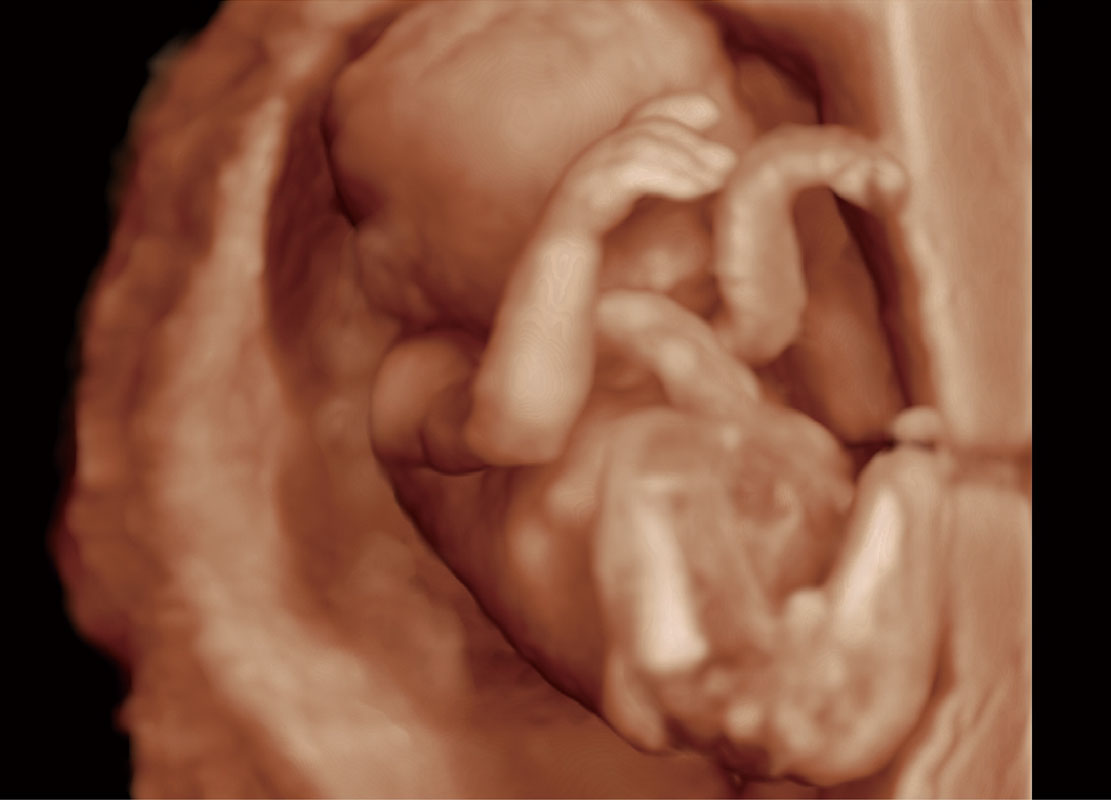

P60在胎儿早孕期超声筛查中为您带来优异的图像质量。

高分辨率容积成像-早孕胎儿

光影成像-孕囊